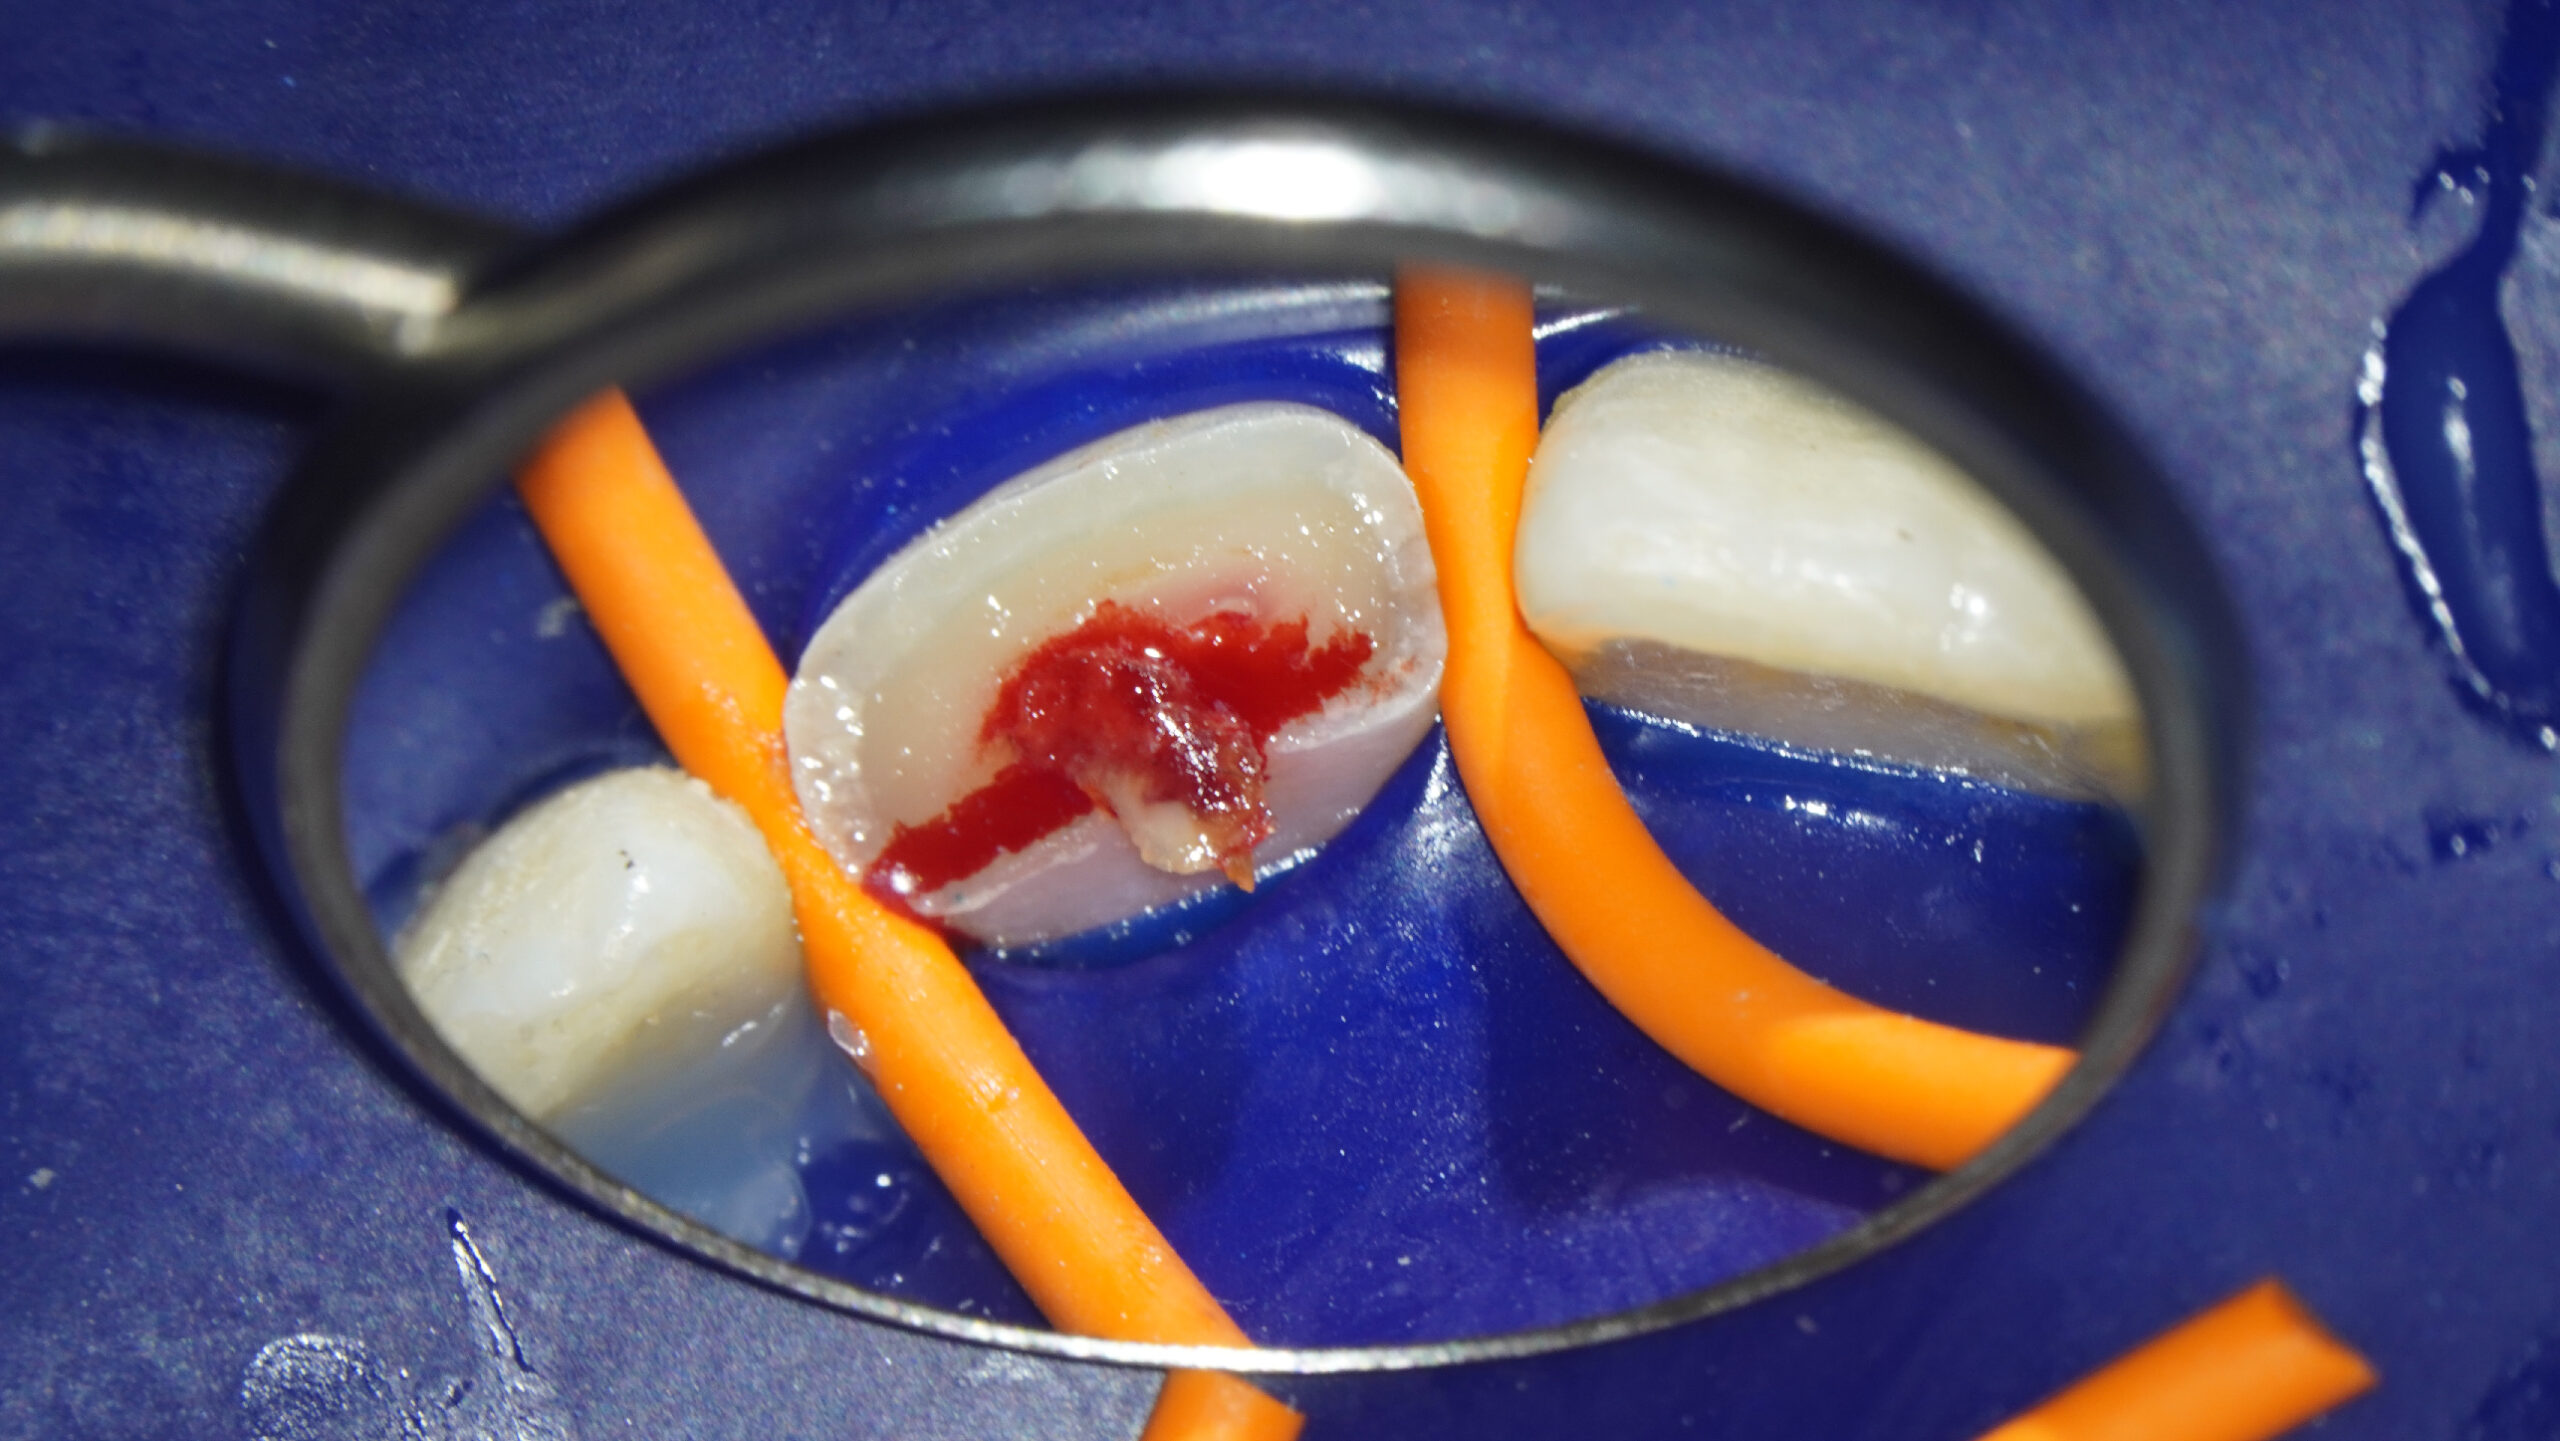

2.1 fractura coronal